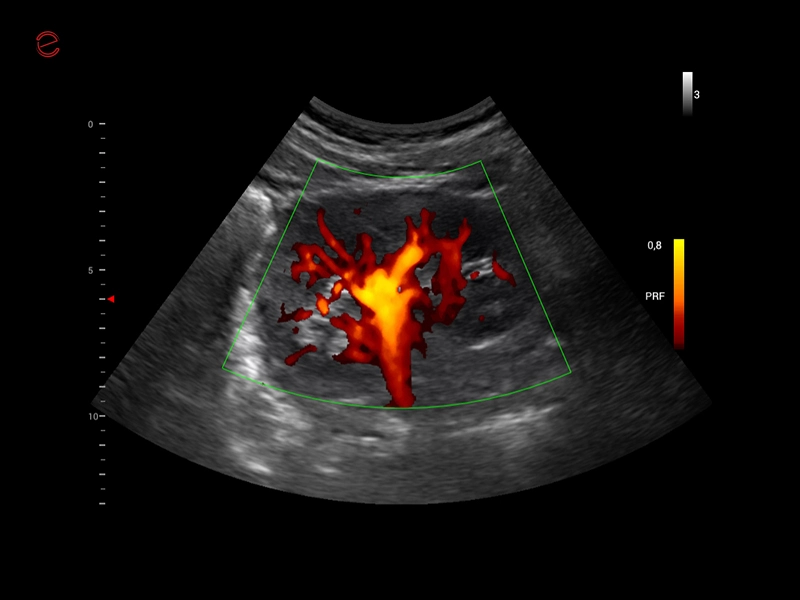

MyLab™C30 - MICROV-NEW

MyLab™C30 - MICROV-NEW